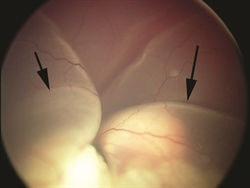

Figure 1: After placement of a speculum to hold the eye open during examination under general anesthesia, the tumor inside the patient’s eye is visible to the naked eye of the examiner. (Photo courtesy of G. Baker Hubbard, MD) |